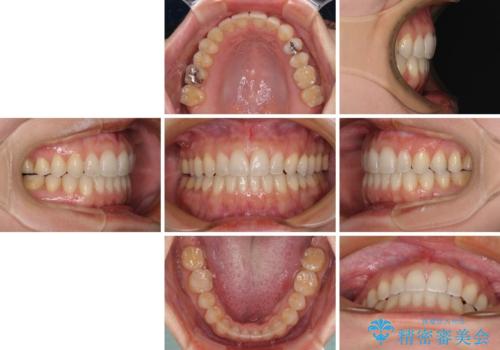

【モニター】狭い上顎歯列とオープンバイト 急速拡大装置を用いた矯正治療

- 前歯の開咬を気にして来院された患者様です。

上顎歯列が狭窄していたため、急速拡大装置により上顎骨を側方に拡大し、その後インビザラインにて矯正治療を行うこととしました。

舌の突出癖が開咬の原因であったので、改善のための舌トレーニングを行っていただきました。

舌トレーニングは後戻りにも大きく影響するため、とても重要なトレーニングです。